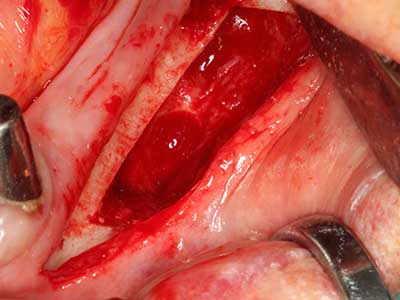

Abb. 17a: CT-Aufnahme eines wachstumsprogredienten Osteoms in unmittelbarer ...

Abb. 17b: Lagebeziehung zum Alveolarkanal mit Nervirritation (laterale und koronare Ansicht).

Abb. 18: Präparation eines Kortikalis-Deckels mit der Piezo-Knochensäge (Piezomed, W&H).

Abb. 19: Operationssitus nach Neurolyse und Osteomentfernung.

Abb. 20: Der entnommene Knochendeckel wird readaptiert und durch eine Osteosyntheseschraube (KLS Martin, Tuttlingen) fixiert.